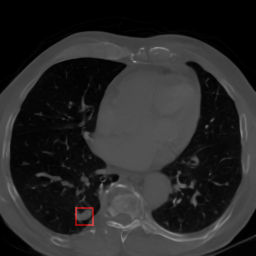

Chest CT synthetic 2D image

Characterization of Synthetic Lung Nodules in Conditional Latent Diffusion of Chest CT Scans

Roger Marí‬, Paula Subías-Beltrán, Carla Pitarch, Mar Galofré, Rafael Redondo

Artificial Intelligence Research and Development, 2024

paper / code / data / doi: 10.3233/FAIA240408

We generate synthetic 2D chest CT imagery using a conditional latent diffusion model guided by bounding-box masks and attribute embeddings. We analyze how well the model controls lung nodule placement and characteristics, highlighting strengths and biases.